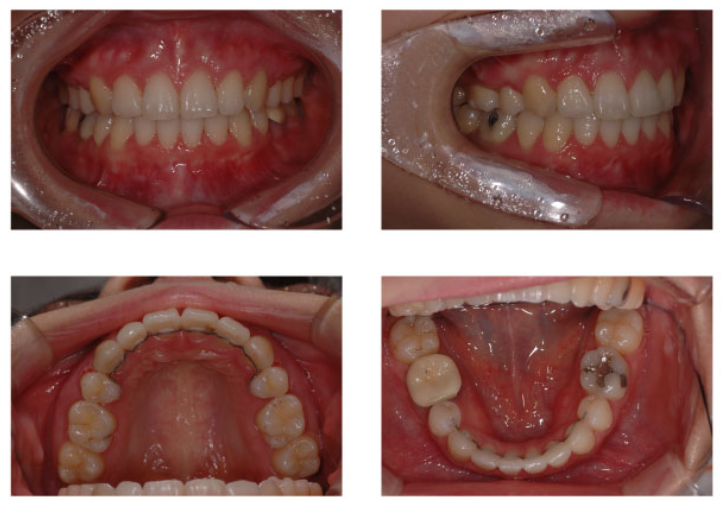

환자 분의 케이스는 돌출입이 심해 입이 다물어지지 않는 경우였는데요.

미니스크류를 통해 후방으로 끄는 힘의 작용점 역할을 하여 악궁 전체를 후방으로는 밀어줄 수 있었습니다.

치아의 뿌리가 상당 부분 전방으로 나와있어도 교정만으로 후방으로 넣을 수 있었던 것이죠.

특히 환자분의 경우 티나지 않는 교정, 순측교정 방식으로 진행을 하였는데요.

미니스크류를 사용해 수술도 하지 않고 상하악 양쪽에서 한 개 씩 치아를 발치해 이동 공간을 마련해 진행이 되었습니다.

이후 환자분의 경과 상태는 불규칙했던 치열도 가지런하게 맞추고

돌출된 입툭튀 부분도 후방으로 잘 당겨주어 안모 변화도 기대해볼 수 있는데요.